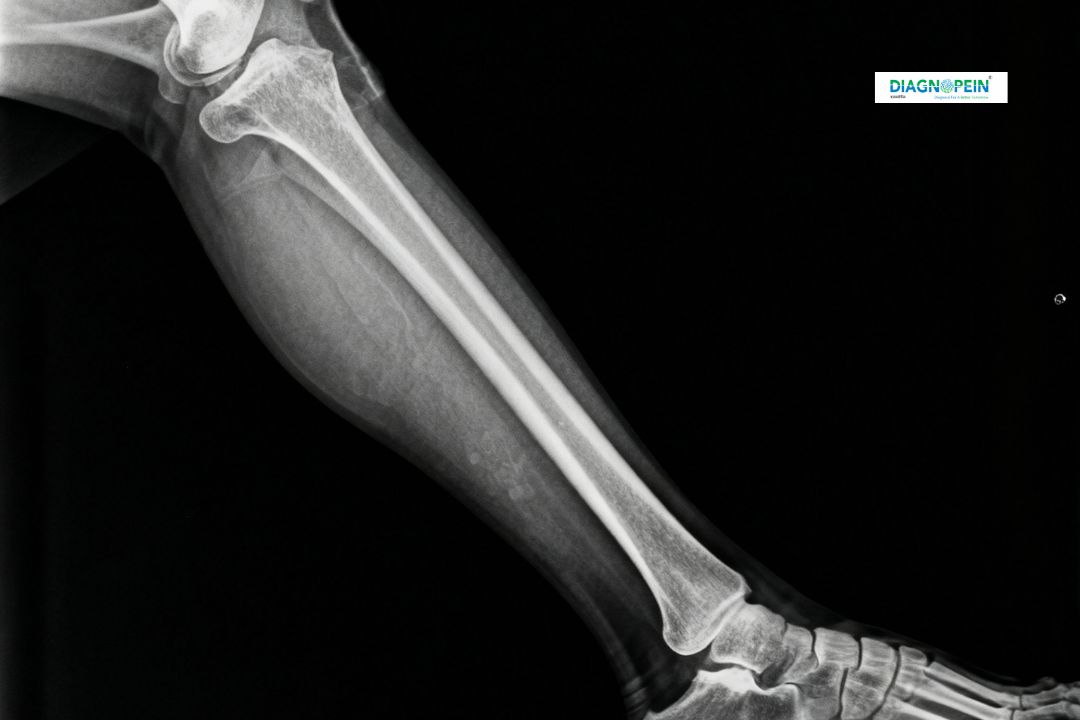

An X-Ray Left Leg AP/OBQ (Anteroposterior and Oblique view) is a specialized imaging procedure used to capture two specific angles of the left leg. The AP view gives a front-to-back image, while the oblique view provides a rotated perspective for a better structural understanding.

This test is essential for detecting injuries, assessing bone alignment, and diagnosing diseases such as fractures, degenerative bone conditions, or infections. At Diagnopein in Karad, we use low-radiation digital X-ray technology which ensures patient safety while delivering high image clarity for doctors to evaluate efficiently.

The X-Ray Left Leg AP/OBQ test at Diagnopein in Karad helps evaluate:

1. Bone fractures or micro-cracks

2. Alignment and joint space

3. Presence of bone tumors or degenerative changes

4. Post-fracture healing progress

5. Abnormal bone densities or infections

Each scan is reviewed by senior radiologists to provide an accurate and detailed report for your treating physician.